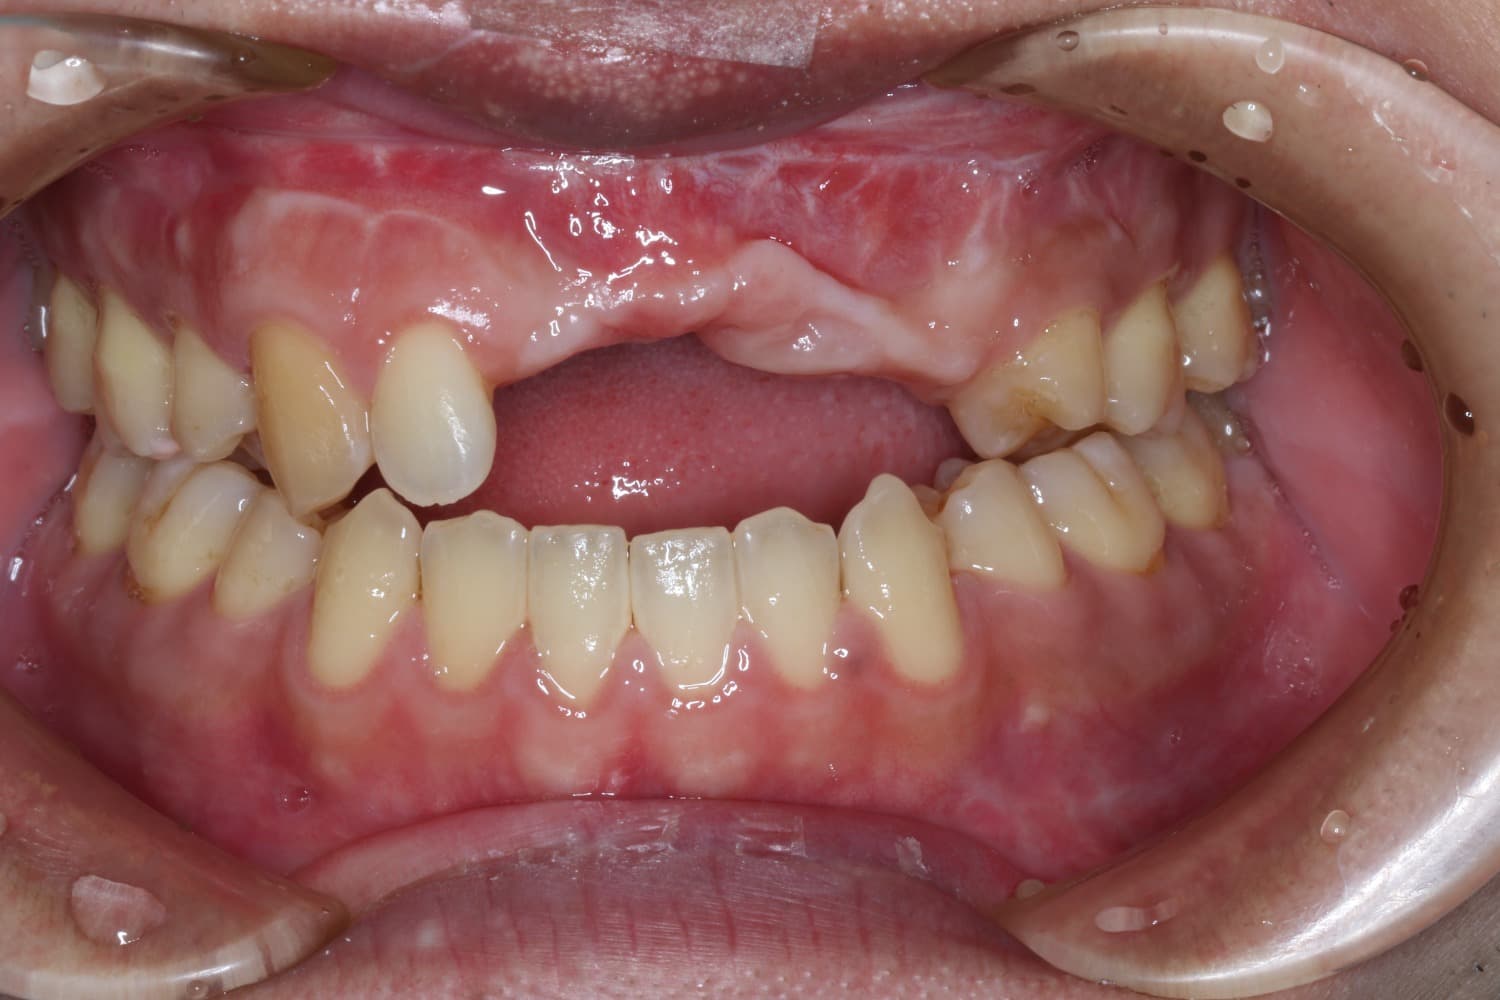

他院でおこなったインプラントの再埋入

Before

右上12に他院にてインプラント治療を行ったが、見た目が悪いのでGBRとCTG、再埋入を行った。

年齢

40代

性別

女性

主訴

歯茎にものが詰まる。見た目が悪い。

治療期間

1年6ヶ月

治療回数

10回

費用

80万円

副作用・リスク

腫脹、疼痛